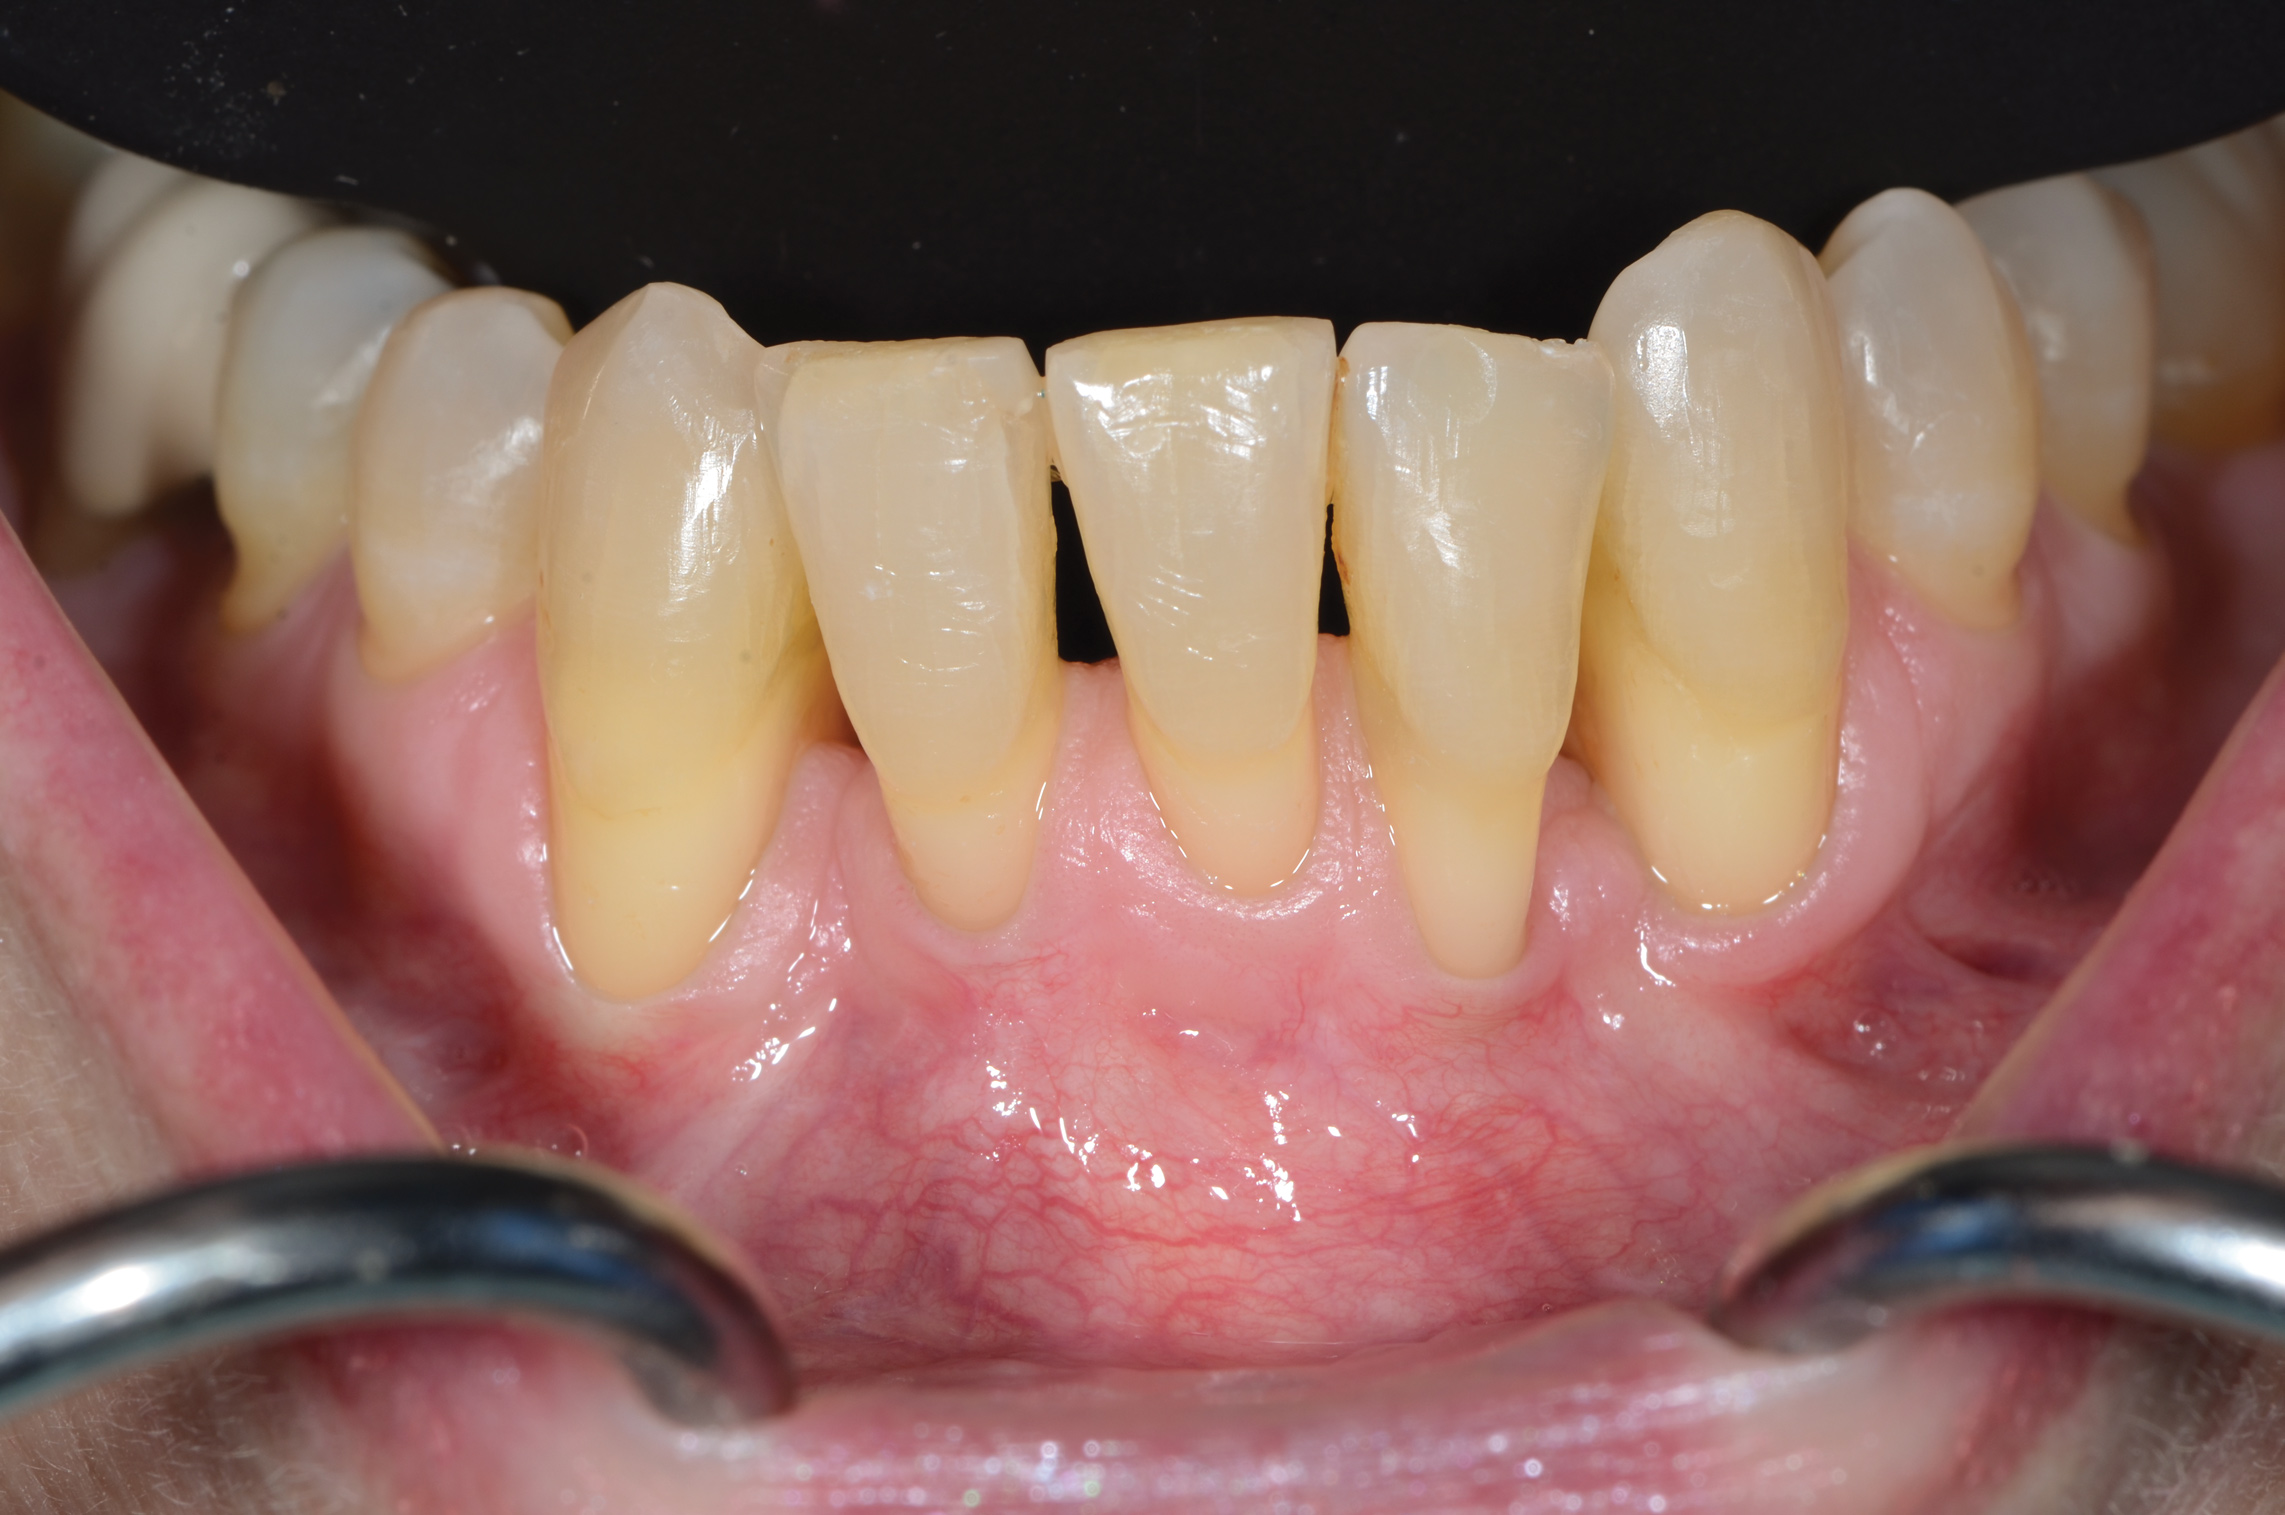

Periodontal Biotype

The association between gingival biotype (thickness) and buccal bone thickness has already been demonstrated through the use of direct measurement and cone-beam computed tomography (CBCT) analysis in cadaver heads.12 The importance of biotype as it relates to the outcome of SFOT has to do with its inherent available osseous and mucosal blood supply (Figure 7 through Figure 9). Osseous blood supply associated with various bone thicknesses and its impact on final outcome and predictability will be discussed in the next section (Alveolar Bone Thickness and Tooth Position). As to gingival/mucosal blood supply, it has been demonstrated that the major blood supply to the gingival tissue originates both from the supra-periosteal region and within the alveolar process itself.13 Therefore, if gingival blood supply is compromised due to deficient alveolar bone in a thin biotype, not only will there be an increased risk for future gingival recession but also compromised blood supply to support the regenerative process and wound healing. From classic literature associated with root coverage, thicker flaps bearing more favorable gingival blood supply have shown an increased predictability for complete root coverage.14

Based on these studies, predictability of generating the buccal plate and enhancing bone and soft-tissue thickness in thin biotype throughout SFOT may be reduced due to a limited mucosal blood supply to nourish both the biomaterial barrier and the flap itself. The use of multiple biomaterials should be considered in compromised thin tissue to avoid tissue sloughing and graft exposure. (Selection of biomaterials related to predictability will be discussed further in the aforementioned tentatively scheduled second article.)

Alveolar Bone Thickness and Tooth Position

For any regenerative procedure, the provision of cells, nutrients, and oxygen through existing blood supply is detrimental.15,16 Blood supply, in contrast to other important though modifiable factors, is the only critical factor that is pre-determined and directly associated with baseline alveolar anatomy. Thus, it is crucial to assess baseline trabecular bone versus cortical thickness and density using a CBCT, especially in the anterior mandible.17,18

Previous classifications of alveolar bone thickness and bony dehiscences have been offered to predict future risk of recession and its association with potential tooth movement. Classifications by both Richman and Evans have suggested a 1 mm to 2 mm bone thickness to minimize risk.2,19 Another classification system differentiates between crestal and radicular bone, allowing for proper planning for orthodontic treatment and future tooth positioning and identifying specific areas of need for augmentation to maximize post-therapy buccal bone thickness.20 This approach can also be adopted for case selection and predicting maximum alveolar bone post-SFOT, while combining grafting procedures with guided tooth movement.19 From a tooth movement perspective, orthodontic-related factors are discussed below. But from a regenerative perspective, a compact bone overlying a thin trabecular layer has a negative effect on blood supply and bone regeneration (Figure 7 and Figure 8).

Case selection related to baseline anatomy of alveolar bone is critical and is the initial step in determining predictability. In the author's opinion, in thin compromised cases modifications may include the use of soft-tissue augmentation only, with a minimally invasive approach, and/or the incorporation of proliferative agents and biologics, such as platelet-rich fibrin or platelet-derived growth factor-ßß, to stimulate or enhance angiogenesis.21